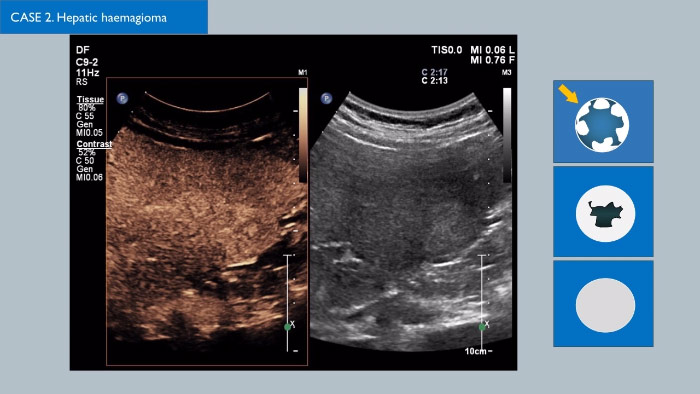

Ultrasonidos con contraste (CEUS)

Los agentes de contraste para ultrasonidos pueden transformar el papel que desempeñan los ultrasonidos, pues permiten que los profesionales sanitarios estudien los patrones de mejora de las lesiones hepáticas en tiempo real, lo que ofrece la posibilidad de realizar diagnósticos más definitivos y rápidos.

Con los ultrasonidos de Philips, los ultrasonidos con contraste se integran a la perfección en el flujo de trabajo normal y proporcionan un nivel de detalle excepcional en exploraciones de la fase arterial, portal y tardía. Además, gracias a tecnologías avanzadas como MaxVue, el transductor PureWave C9-2, las imágenes de fusión, la cuantificación integrada mediante las Q-App de Philips y la solución hepática definitiva, ya es posible sentir una seguridad total incluso en las exploraciones más complicadas. Soluciones innovadoras como la tecnología xMATRIX 3D/4D también pueden dar un giro a la evaluación de las lesiones hepáticas, pues proporcionan un método rápido y eficaz de visualizar los vasos nutricios y la respuesta al tratamiento. Existen multitud de avances fascinantes en el campo de los CEUS; haga clic en el enlace para ponerse en contacto con su representante local de Philips.